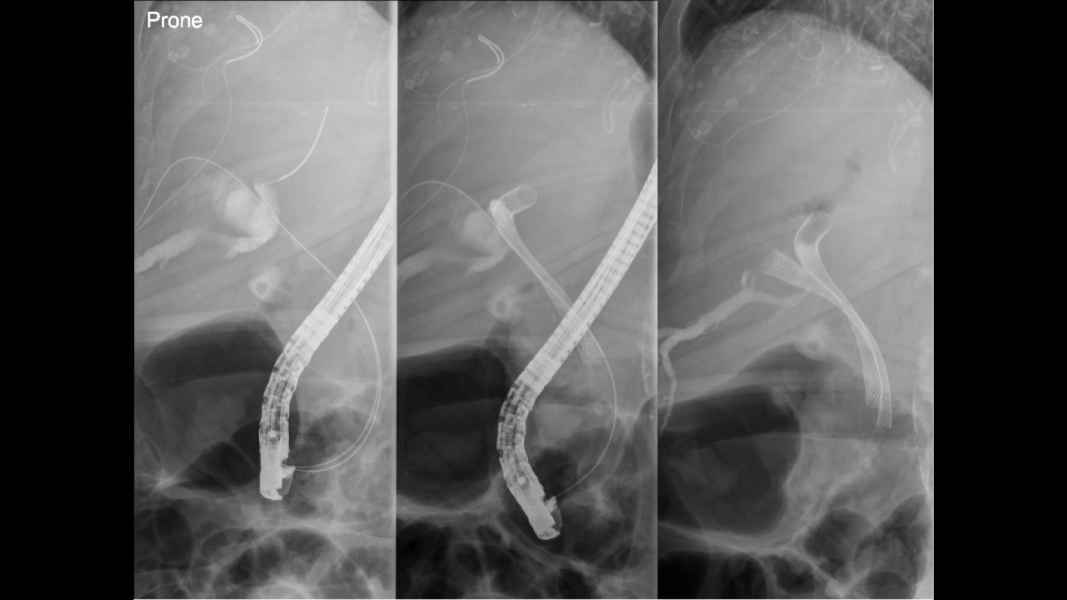

Estenose de Anastomose Hepatico-jejunal com litíase intra-hepática – Tratamento por CPRE com Enteroscópio

Fotografia